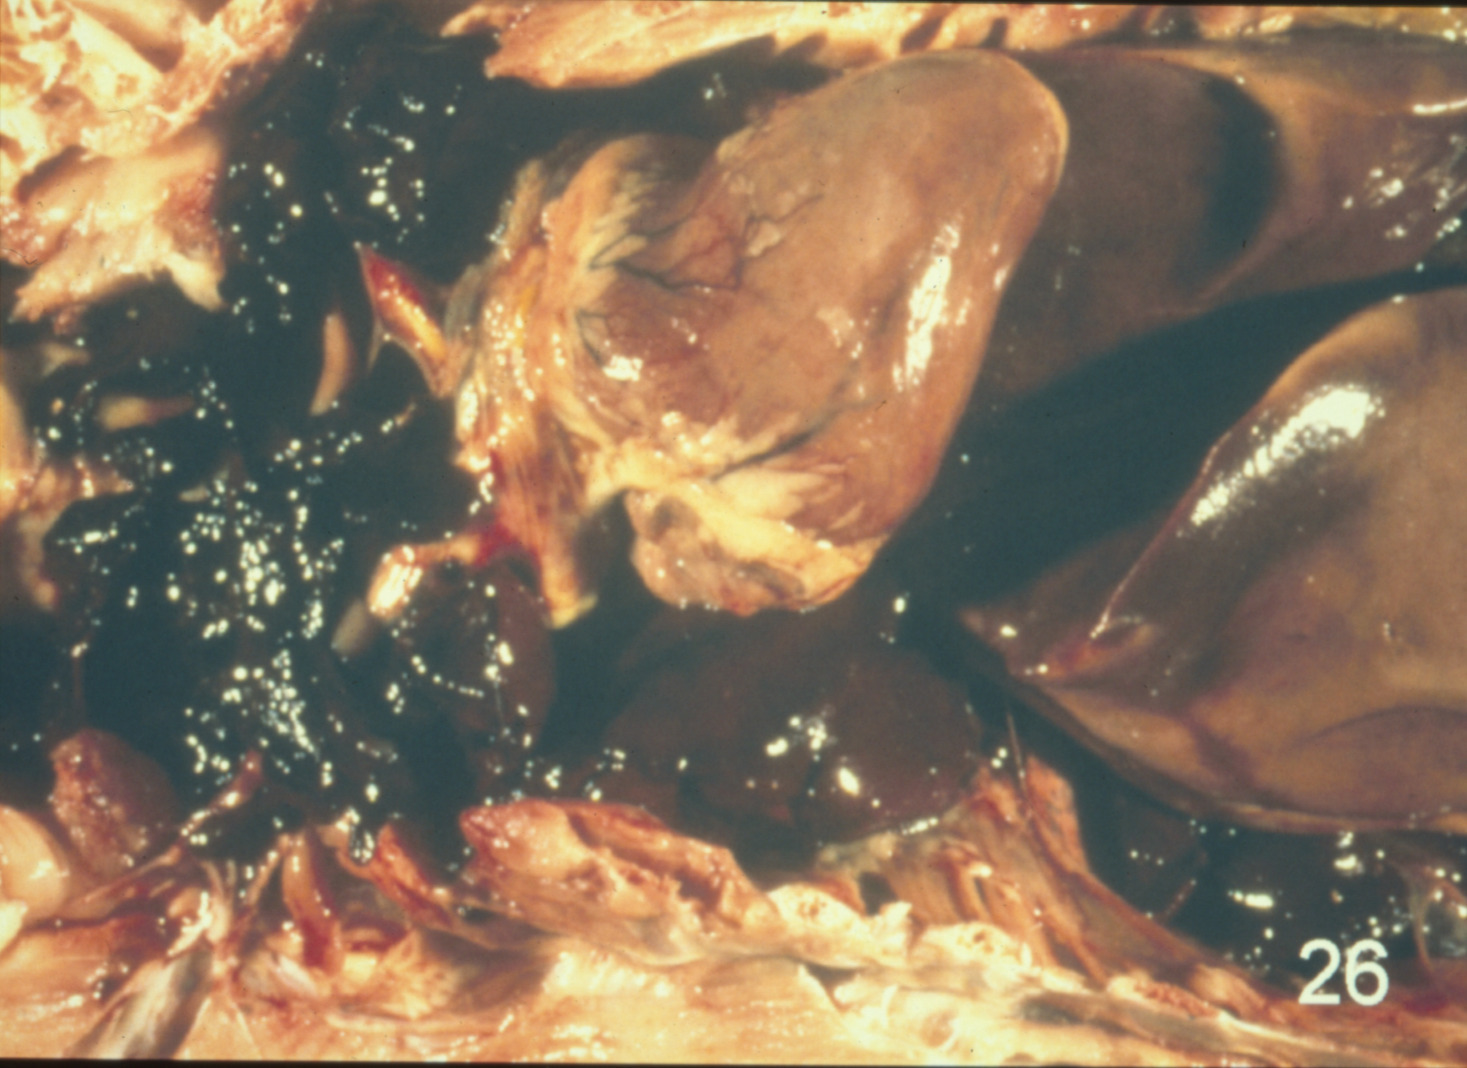

Cardiovascular disease in turkeys (slide study set no. 24)

Turkeys--Diseases Cardiovascular system--Diseases

Slide Study Set #24, Cardiovascular Diseases in Turkeys (includes 27 color slides), 2001